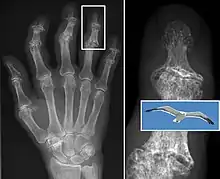

In 1990, the American College of Rheumatology, using data from a multi-center study, developed a set of criteria for the diagnosis of hand osteoarthritis based on hard tissue enlargement and swelling of certain joints.[55] These criteria were found to be 92% sensitive and 98% specific for hand osteoarthritis versus other entities such as rheumatoid arthritis and spondyloarthropathies.[56]

Bone (left) and clinical (right) changes of the hand in osteoarthritis

In smaller joints, such as at the fingers, hard bony enlargements, called Heberden's nodes (on the distal interphalangeal joints) or Bouchard's nodes (on the proximal interphalangeal joints), may form, and though they are not necessarily painful, they do limit the movement of the fingers significantly. Osteoarthritis of the toes may be a factor causing formation of bunions,[16] rendering them red or swollen.